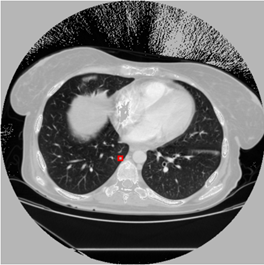

原图:

预测:

标注图(根据标注生成):

在应用yolov3算法进行肺结节检测时,发现其在实际应用中仍存在一定局限性。具体表现为:1)迭代训练不足导致模型尚未达到充分收敛的状态;2)有必要对训练数据集进行聚类分析以优化参数设置,并调整anchor框大小与比例参数设置以进一步提升检测精度。